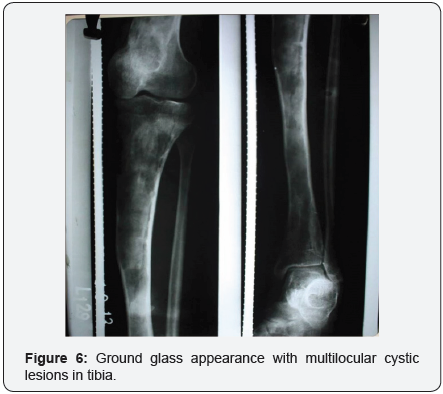

X-rays features are not specific although they may be characteristic depending on the underlying histopathological picture. These features range from unilateral fusiform enlargement of medulla, deformity with cortical thickening, increased trabeculation to a characteristic “ground-glass” appearance which is formed by a mixture of immature bone and fibrous tissues [2,7]. On CT scan amorphous or irregular calcification may be seen. Magnetic resonance imaging maybe used in accurately defining full extent of the lesion.

- Multiple multilocular cystic lesions with ground glass diffuse rarefactions throughout the bone with mid shaft transverse fracture.

- Similar lesions were seen in B/L Proximal humerus and Rt pelvis.